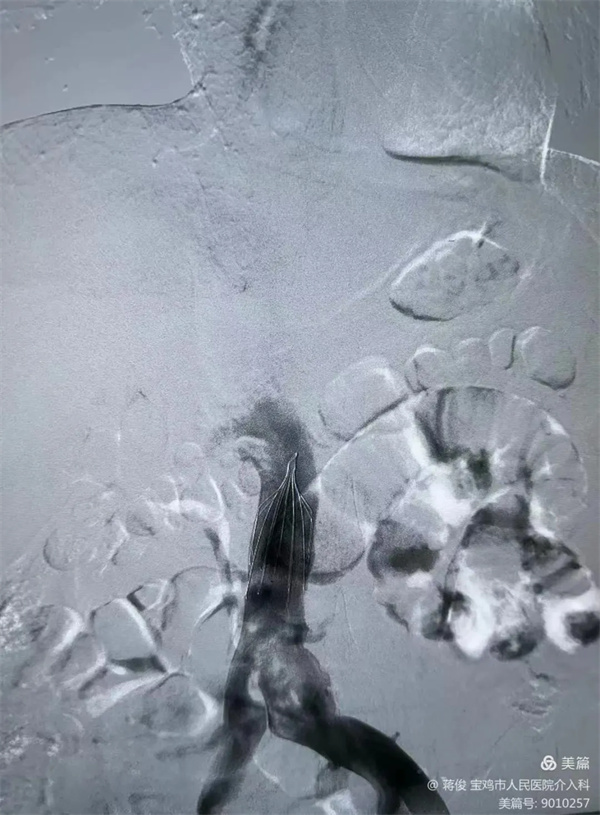

置入下腔靜脈濾網,預防下肢靜脈血栓再次脫落